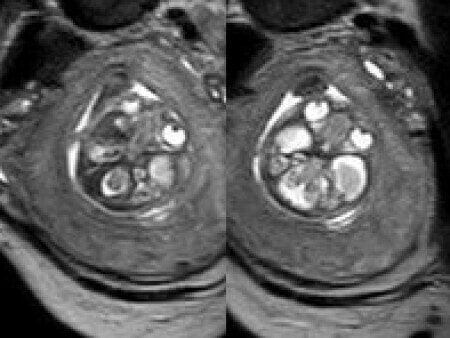

At 20 weeks, detailed ultrasound under conditions of severe oligohydramnios demonstrated absence of the typical box-shaped anechoic structure of the cavum septum pellucidum (CSP). The frontal horns of the lateral ventricles appeared narrow and pointed, giving the characteristic “bull’s horns sign.” Multiplanar and 3D reconstructions confirmed the presence of the corpus callosum, while the CSP was absent. Other midline and posterior fossa structures appeared normal. The optic chiasm was partially visualized, although assessment was limited by technical conditions. Fetal magnetic resonance imaging (MRI) was subsequently performed and confirmed isolated agenesis of the CSP with preserved corpus callosum and posterior fossa structures. The optic chiasm and pituitary stalk are visible in the sellar region, but the pituitary gland itself is not clearly identified in the sella turcica as it is a very small structure. No additional central nervous system anomalies were detected.